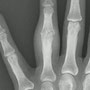

Bei schwere Zerstörung der Fingergelenke kann es notwendig sein, das Gelenk zu ersetzen. Mitunter ist ein Ersatz mehrerer Gelenke notwendig. Vereinzelt ist die Operation auch ambulant möglich. Das Bild zeigt die momentan eingesetzte Silastikprothese Neuflex der Firma de Puy.